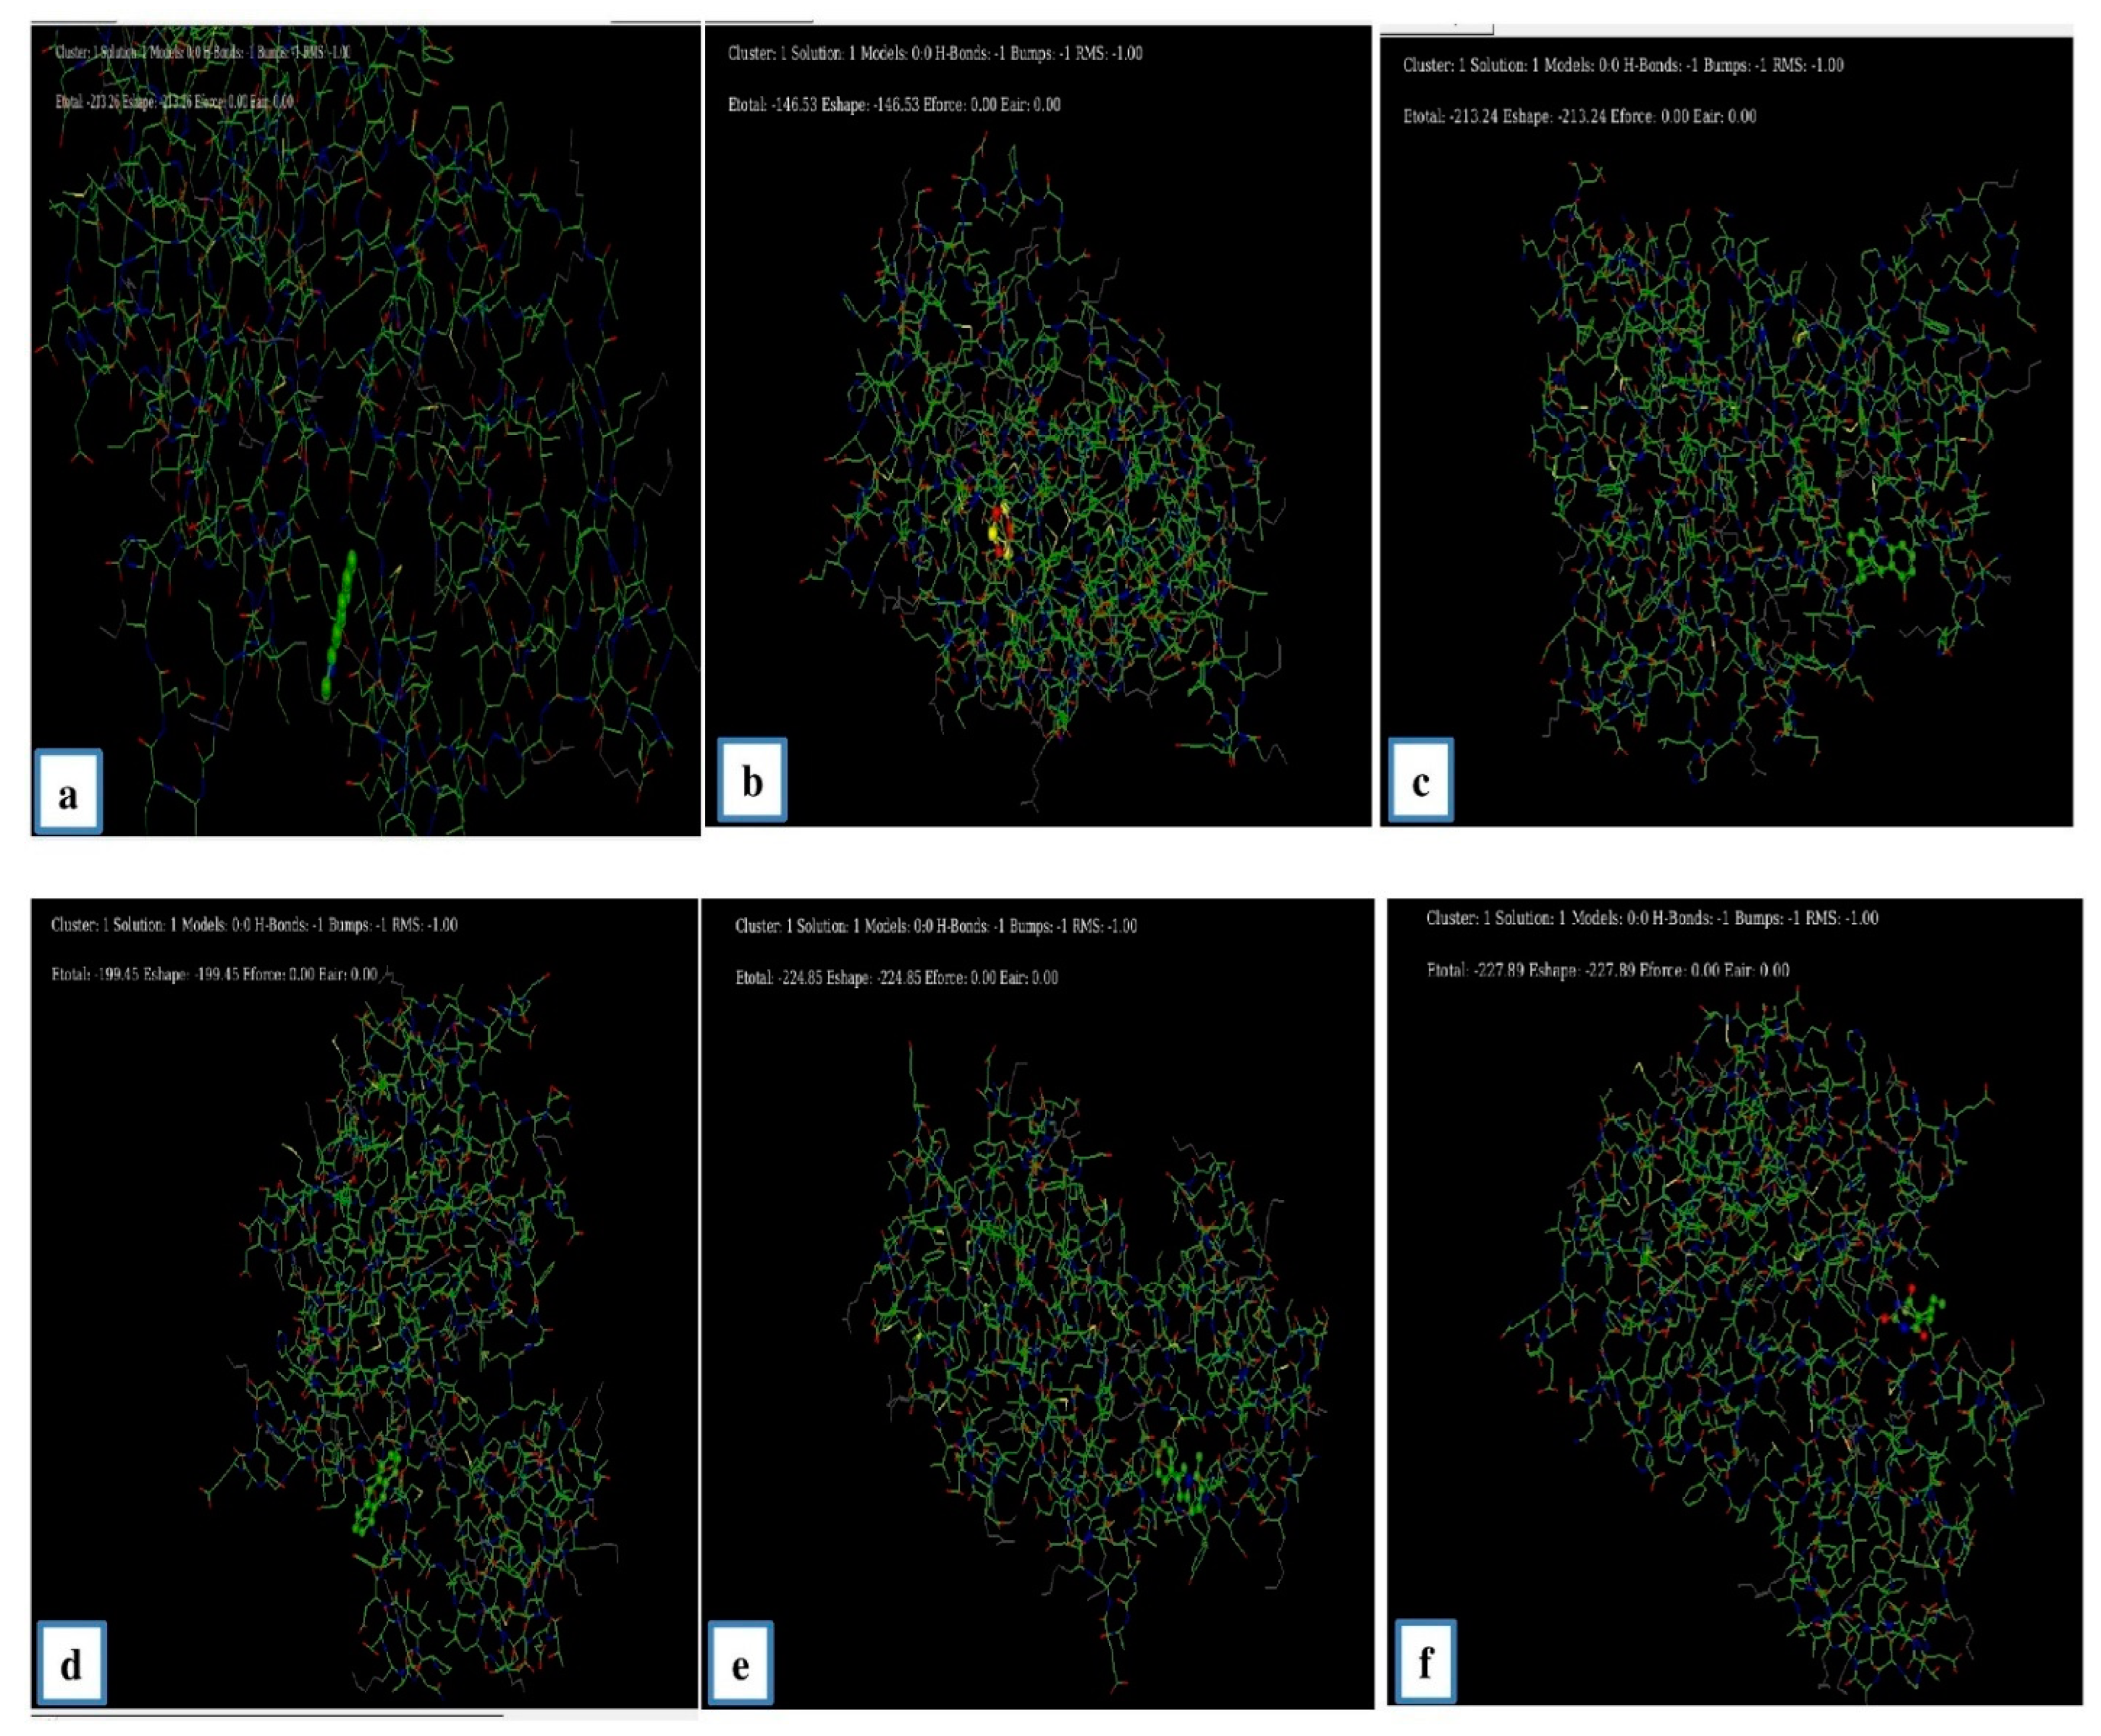

3.6.3. Molecular Docking Study

| Ligand | E min |

|---|---|

| Benzo [h] quinolone | −213.20 |

| Cyclotrisiloxane | −146.53 |

| Ethylacridine | −213.24 |

| Anthracene | −199.45 |

| 5 methyl 2 phenylindolizine | −224.85 |

| Brallobarbital | −227.89 |